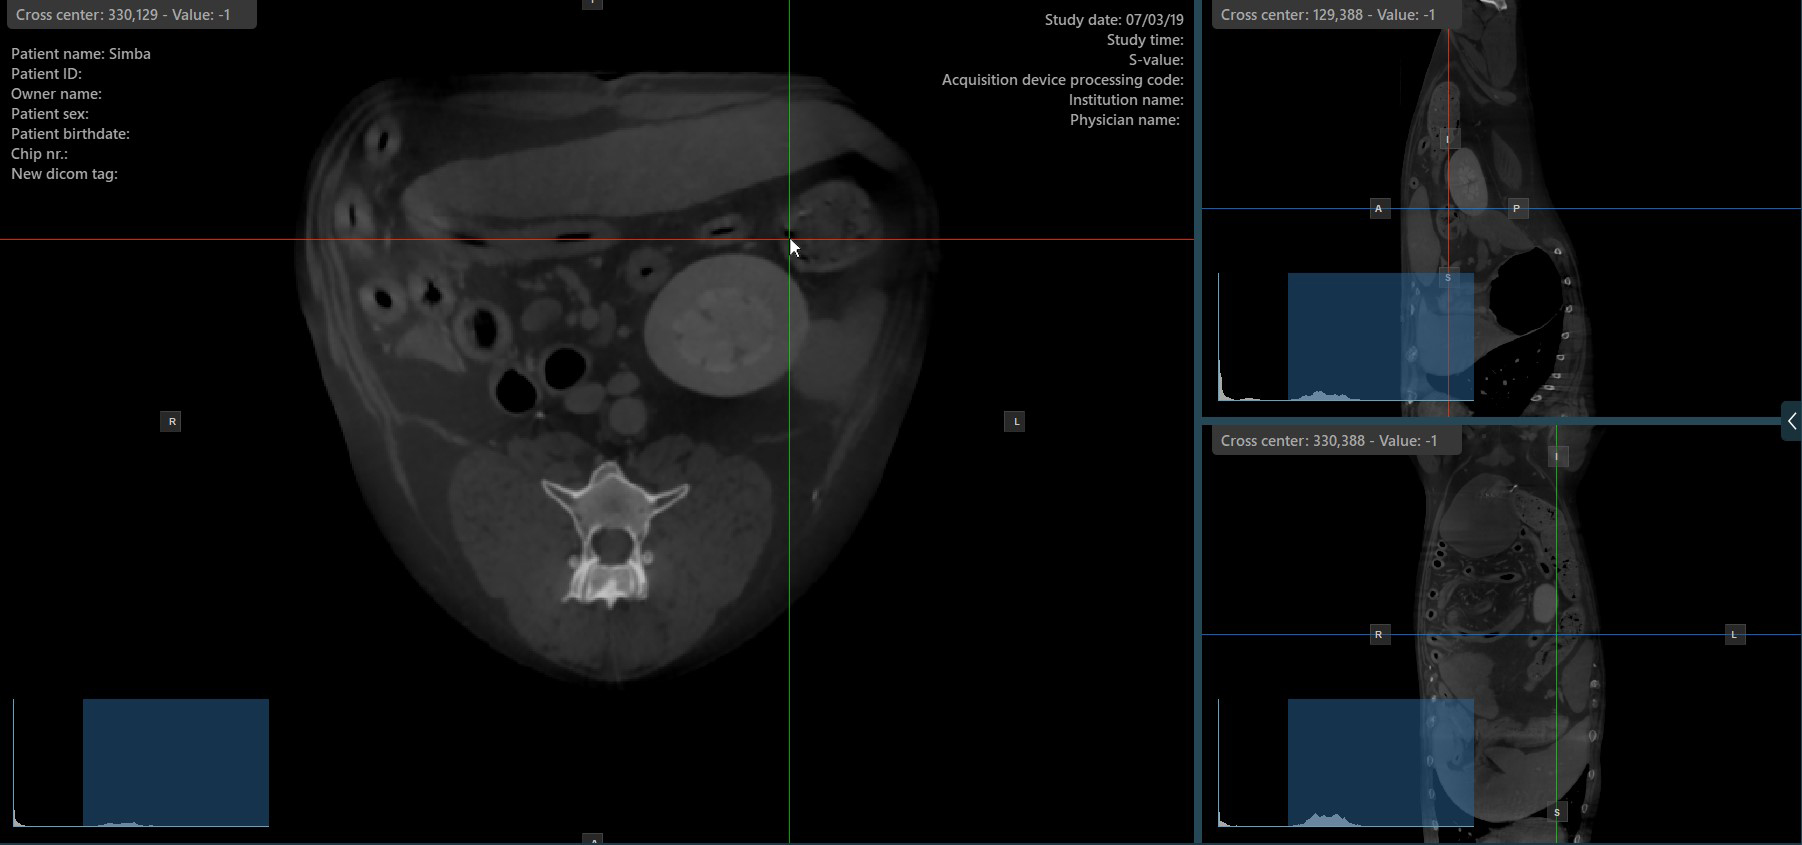

Change Slicers Cross Center Position¶

Altering the position of the cross center of slicers will change the position of the corresponding two image planes. The cross center of the slicers can be selected by using the Select Item (Default)

tool, assigned to the right mouse

button by default.

Once selected, drag the cross center of the specific slicers to the desired direction to move its position. The corresponding image planes» orientation changes accordingly.